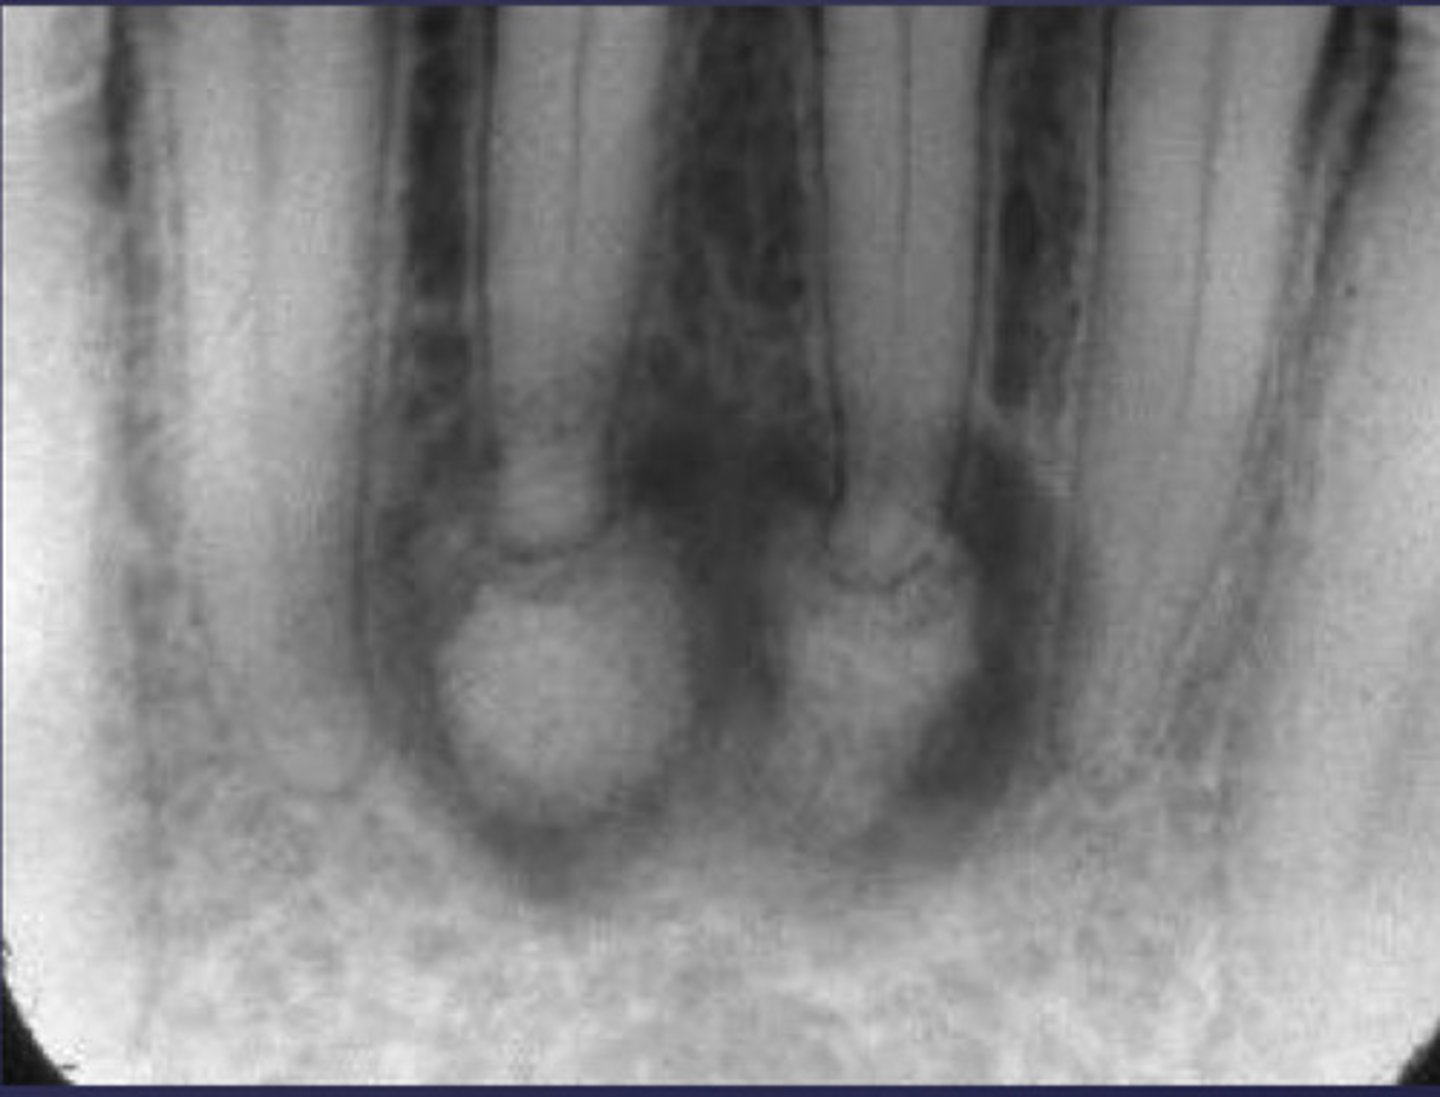

How would you describe the following lesion?

Multiple mixed density periapical target-like entities

The teeth are vital. What category would you put this lesion into?

dysplasia (PCOD)

what could be a differential diagnosis for this lesion?

A. radicular cyst

B. periapical granuloma

C. PCOD (stages 2/3)

D. apical rarefying osteitis